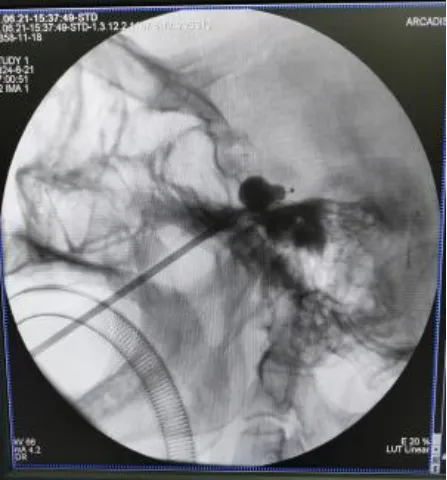

近日,陕西省中医医院脑病医院神经外科团队开展的介入引导下三叉神经半月节微球囊压迫术,通过面部穿刺卵圆孔,在三叉神经半月节处释放微球囊,卡压神经纤维、阻滞痛觉传导,立竿见影地为患者消除了三叉神经痛。

患者杨女士右侧眼窝频发、剧烈疼痛2年,吃饭、洗脸时常常诱发,疼痛难以忍受。曾在多家三甲医院诊治,行磁共振检查提示三叉神经脑池段有血管接触,诊断为三叉神经痛,服用卡马西平,近一年效果不佳,建议患者开颅行微血管减压术,患者及家属难以接受开颅手术,遂来我院。入院追问病史,患者近2年曾有数次失语、左上肢无力发作,术前MRA检查提示颅内动脉多发狭窄,脑二科及神经外科团队讨论后,考虑开颅手术风险大,结合患者病情及家属意愿,于6月21日在手术室、麻醉科的配合下,予以全麻下行三叉神经痛球囊压迫手术,术后右侧眼窝疼痛消失,除右侧面部感觉稍减退外,无其它并发症,家属感到相当满意,患者也露出了满意的笑容。

三叉神经球囊扩张压迫术属于微创手术,只需面部一个小小穿刺点,将球囊送入三叉神经半月节、扩张球囊压迫三叉神经即可,手术相对安全,费用低、时间短、损伤小、恢复快,住院时间短,尤其适用于高龄体弱,有高血压、糖尿病等基础疾病不适宜开颅手术以及已经接受开颅手术后再次复发的患者。